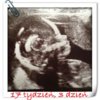

No jak parka to wiadomo, że dwujajoweja liczyłam też na parkę więc też mam ciąże dwujajową czyli jeszcze tą najbezpieczniejszą z bliźniaczych a fachowo jak się ostatni dowiedziałam to dwujajowe to nawet nie bliźniaczki tylko dwojaczki czyli jakby dwie ciąże w jednym czasie